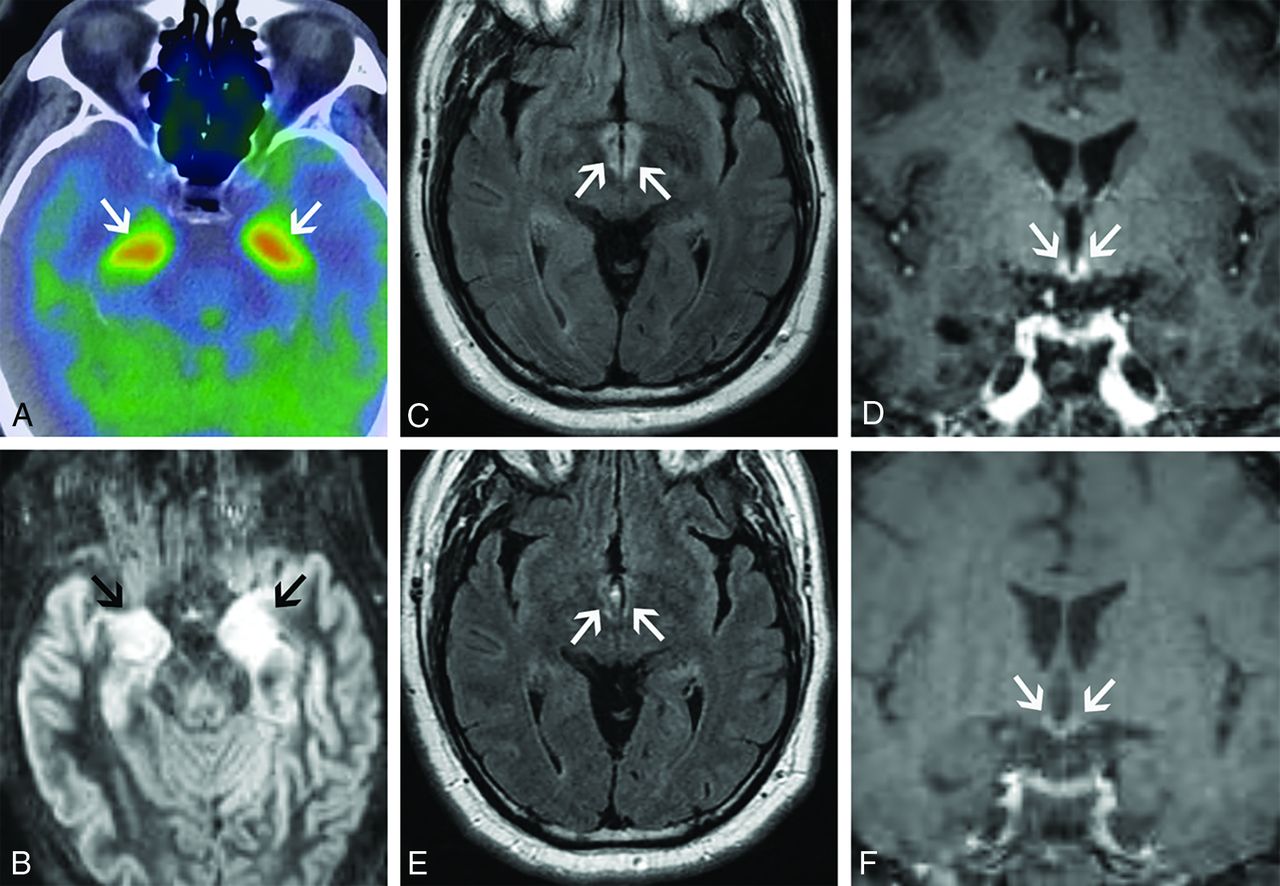

Imaging findings can be normal in these patients. When present, findings vary depending on the phase of illness. Acutely, T2 hyperintensity and/or enhancement of the cerebellum, cerebellar peduncles, and brain stem are seen. Importantly, there can be isolated involvement of the brain stem in the acute phase, which can be mistaken for other entities, including tumor (Fig 5A, -B). As the disease progresses, cerebellar and brain stem atrophy are often seen. Additionally, cruciform T2 hyperintensity in the pons and T2 hyperintensity in the middle cerebellar peduncles can occur with this syndrome secondary to Wallerian degeneration, quite similar to the imaging findings seen in multiple system atrophy (Fig 5C, -D). Hypertrophic olivary degeneration can also be seen as a result of paraneoplastic brain stem encephalitis (Fig 5E, -F), presumably caused by disruption of the dentato-rubro-olivary pathway.

Paraneoplastic brain stem encephalitis mimicking a tumor (A–D). A 29-year-old man presented with tinnitus, hearing loss, diplopia, and imbalance that had progressed over at least 1 year. After extensive clinical work-up, the patient was diagnosed with metastatic seminoma to the mediastinum and noted to have elevated CSF IgG. Serum and CSF were positive for Kelchlike protein 11 autoantibodies. Sagittal T1-weighted postcontrast (A) and sagittal FLAIR (B) images show enhancing, T2 hyperintense lesions in the midbrain and tectum (A and B, arrows), initially believed to be worrisome for metastases. He was treated with chemotherapy, and his symptoms transiently improved but then worsened over the next several years. Sagittal T1-weighted postcontrast (C) and axial FLAIR (D) images from a subsequent MR imaging 4 years later show new marked cerebellar and brain stem atrophy (C, arrows), as well as new T2 signal in the middle cerebellar peduncles (D, arrows) and cruciform T2 signal in the pons (D, arrowhead). He was diagnosed with paraneoplastic brain stem encephalitis rather than multiple system atrophy given the clinical context of the findings. The patient’s symptoms mildly improved after treatment with multiple immunosuppressive agents. Brain stem encephalitis associated with hypertrophic olivary degeneration (E and F). A 45-year-old man presented with progressive aural fullness and hearing loss, initially thought to be caused by otitis media. Over the next 2 years, he had progressive gait ataxia and diplopia. CSF analysis showed antibodies to Kelchlike protein 11. Testicular sonography, performed as part of his oncologic work-up, showed a right testicular mass. Right orchiectomy revealed a germ cell neoplasm. Axial FLAIR images (E and F) from his brain MR imaging show enlargement and T2 hyperintensity of both inferior olives (E, arrows) consistent with bilateral hypertrophic olivary degeneration. Additionally, there is patchy T2 hyperintensity in the cerebellar vermis (F, arrows). He was diagnosed with paraneoplastic rhombencephalitis with associated hypertrophic olivary degeneration. He has had a partial response to multiple immunotherapies.